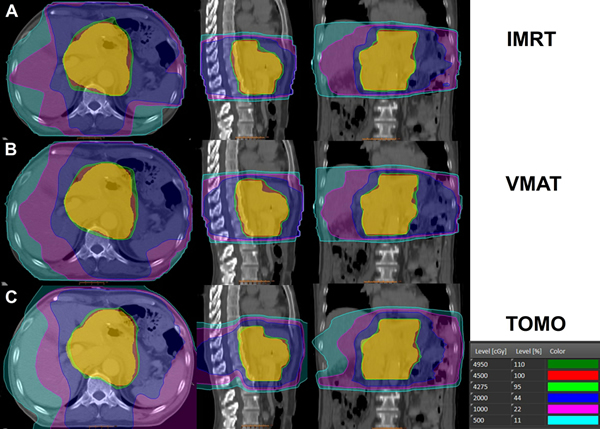

The mean volume of the PTV was 960.61 ± 287.59 cm3. Detailed results of dosimetric comparison for the PTV are shown in Table 1. Among the three plans, TOMO showed the best dose conformity and homogeneity compared to IMRT (p < 0.05) and VMAT (p < 0.01, Figure 1). The mean dose (Dmean) to the PTV was acceptable for all treatment plans, with no statistically significant differences between the three techniques. Figure 2 shows examples of PTV dose distributions obtained for IMRT, VMAT and TOMO plans in a patient who underwent distal partial gastrectomy.

Figure 2: Examples of planning target volume (PTV) dose distributions used for a. IMRT, b. VMAT, and c. TOMO in a patient who underwent distal partial gastrectomy.